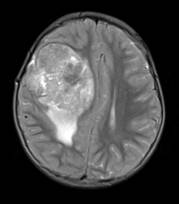

2.頭痛で来院された患者様の頭部MR画像

症状は軽度でも、巨大な脳腫瘍が指摘されました。軽い症状でもまずは医師にご相談ください。